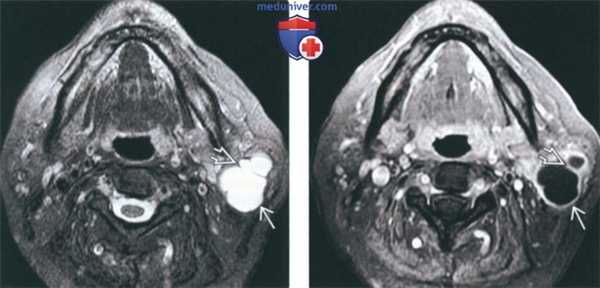

о Характерный признак — неоднородность паренхимы![КТ, МРТ при опухоли Уортина]()

(Слева) На аксиальной МРТ (Т2 ВИ FS) в доле околоушной железы визуализируется гиперинтенсивная опухоль в с перегородками. Кистозную опухоль Уортина можно спутать с простой кистой.

(Справа) На аксиальной MPT (Т1 ВИ С+ FS) у этого же пациента визуализируется гипоинтенсивная опухоль с перегородками и контрастирующимся «ободком». Контрастирование помогает отличить опухоль Уортина от пропой костной кипы, но и позволяет прийти к ошибочному заключению о паротидном абсцессе. Обратите внимание на отсутствие уплотнения окружающей жировой клетчатки, что нетипично для абсцесса.2. КТ при опухоли Уортина:

Опухоль Уортина. Последовательность STIR, фронтальная проекция (а): гиперинтенсивное образование в нижней части правой околоушной железы. На Т1 -взвешенном изображении (b) образование гипоинтенсивно по отношению к железистой ткани.

В горизонтальной проекции наблюдается высокая интенсивность сигнала переднего кистозного компонента на Т2-взвешенном изображении (а) и низкая интенсивность сигнала на Т1 -взвешенном изображении после введения гадолиния (b). Солидный задний компонент усиливается на Т1 -взвешенном изображении (b).